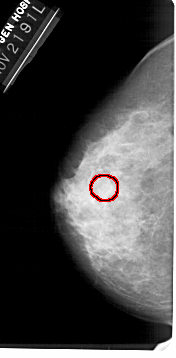

FILE: A_1449_1.LEFT_CC.OVERLAY

TOTAL_ABNORMALITIES 1

ABNORMALITY 1

LESION_TYPE CALCIFICATION TYPE AMORPHOUS DISTRIBUTION CLUSTERED

ASSESSMENT 4

SUBTLETY 2

PATHOLOGY BENIGN

TOTAL_OUTLINES 1

BOUNDARY